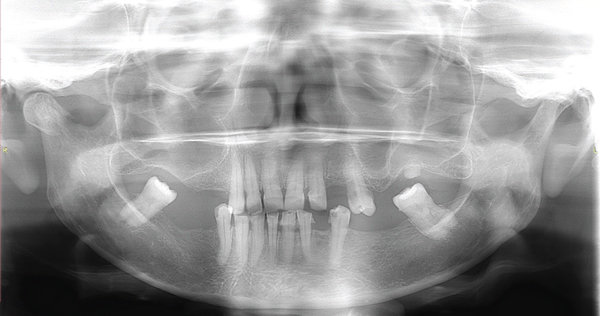

17. (Select ONE OR MORE correct answers)

Which of the following findings is associated with the lower left side of mandible?